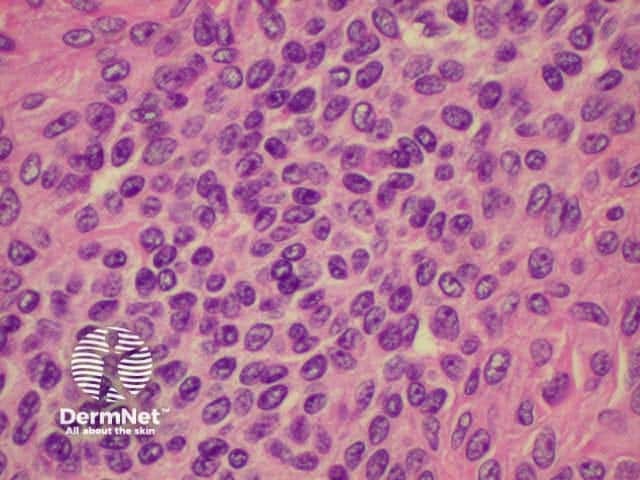

Histology is shown below.

Histology of intradermal naevus  Superficial epithelioid naevus cells  Deeper small dark naevus cells